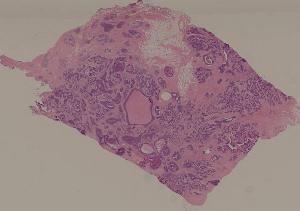

75.慢性硬化性肾小球肾炎

76.急性肾盂肾炎

77.慢性肾盂肾炎

41.肺机会性感染

71.急性肾移植排异反应

72.狼疮性肾炎

36.恶性淋巴瘤

80.乳腺浸润性导管癌

84.Graves病

93.流行性脑脊髓膜炎

94.乙型脑炎

88.慢性纤维空洞性肺结核

89.淋巴结结核

90.皮肤瘤型麻风

91.结核样性麻风

92.肠伤寒

95.脊髓灰质炎

96.肺曲菌病

97.结肠阿米巴病

98.结肠血吸虫病